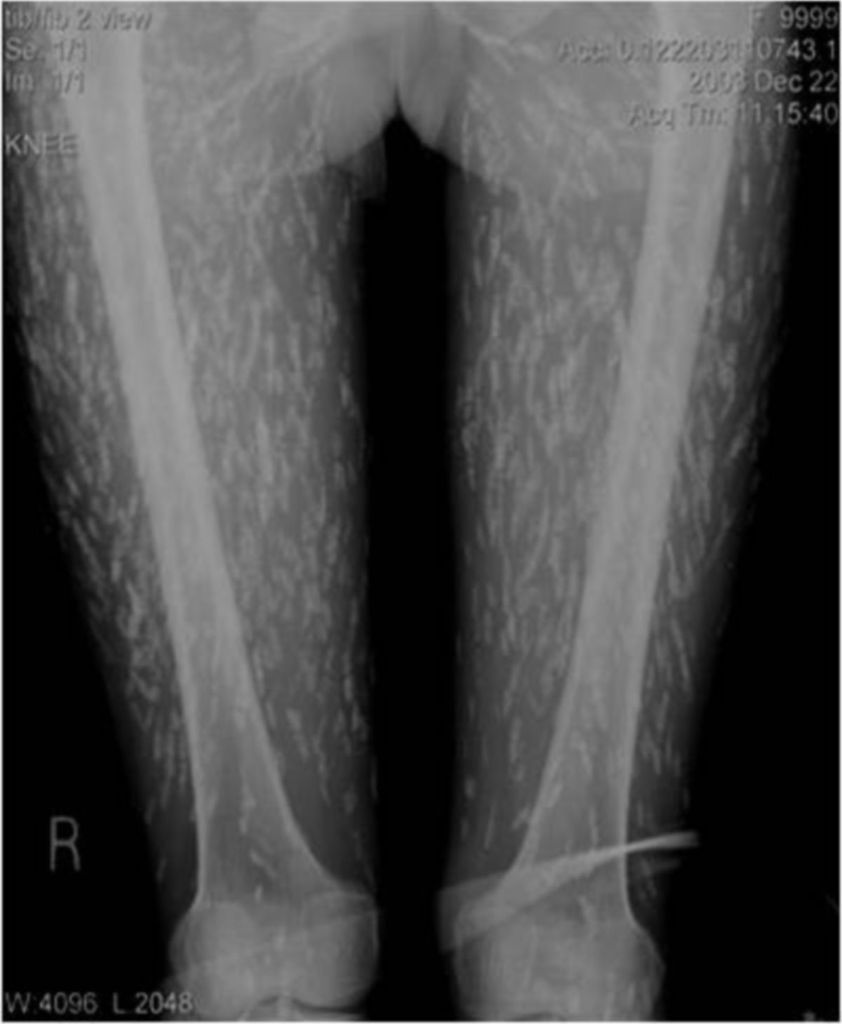

C'est quoi le truc noir

Kj-Cage

des parasites le tenia solum